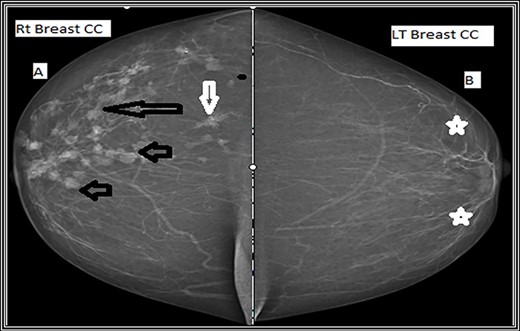

Craniocaudal mammographic view. (A) The right breast shows multiple variable size dense mass lesions, showing regularly lobulated borders (short black arrows), indistinct borders (long black arrow) and speculated outer borders (short white arrow). (B) The left breast shows scattered areas of fibroglandular densities (white stars).